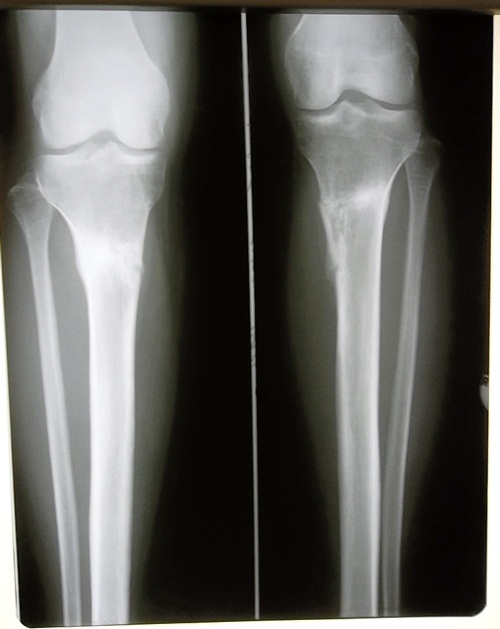

Исходник.

Стопы ещё до операции несколько завалены вовнутрь, особенно слева + плоскостопие. При исправлении О- образной деформации, завал стопы будет усиливаться, по этому с первых дней после операции, необходимо ношение обуви с косячками 0,6 - 0,7 см по внутренней поверхности на подошве.

Дата операции 16.01.2013г.

Дата снятия аппаратов 05.04.2013г.

Срок лечения 77 дней.